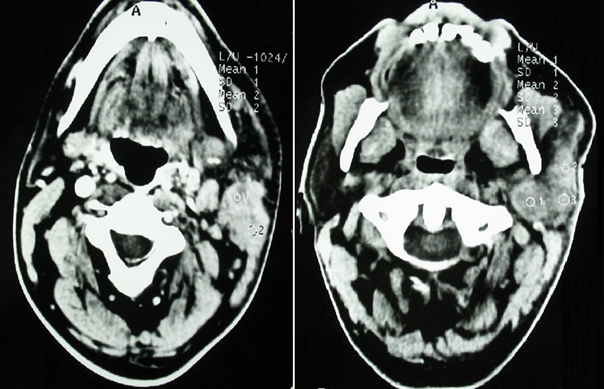

Parotid ultrasound showed an enlarged parotid with a heterogeneous tumor, poorly defined, and hyper vascularized on Doppler, associated with multiple satellite adenopathies (Figure 1). Computed tomography (CT) scan showed a parotid swollen by a parenchymal tumor, hypodense, heterogeneous, and enhancing heterogeneously after injection of contrast product. This tumor infiltrated the peri-parotid fat with multiple adenopathies of secondary appearance (Figure 2 & 3).

Figure 3 Axial CT scans of the parotid gland, with contrast: parenchymal parotid gland tumor enhancing heterogeneously after injection of contrast product.